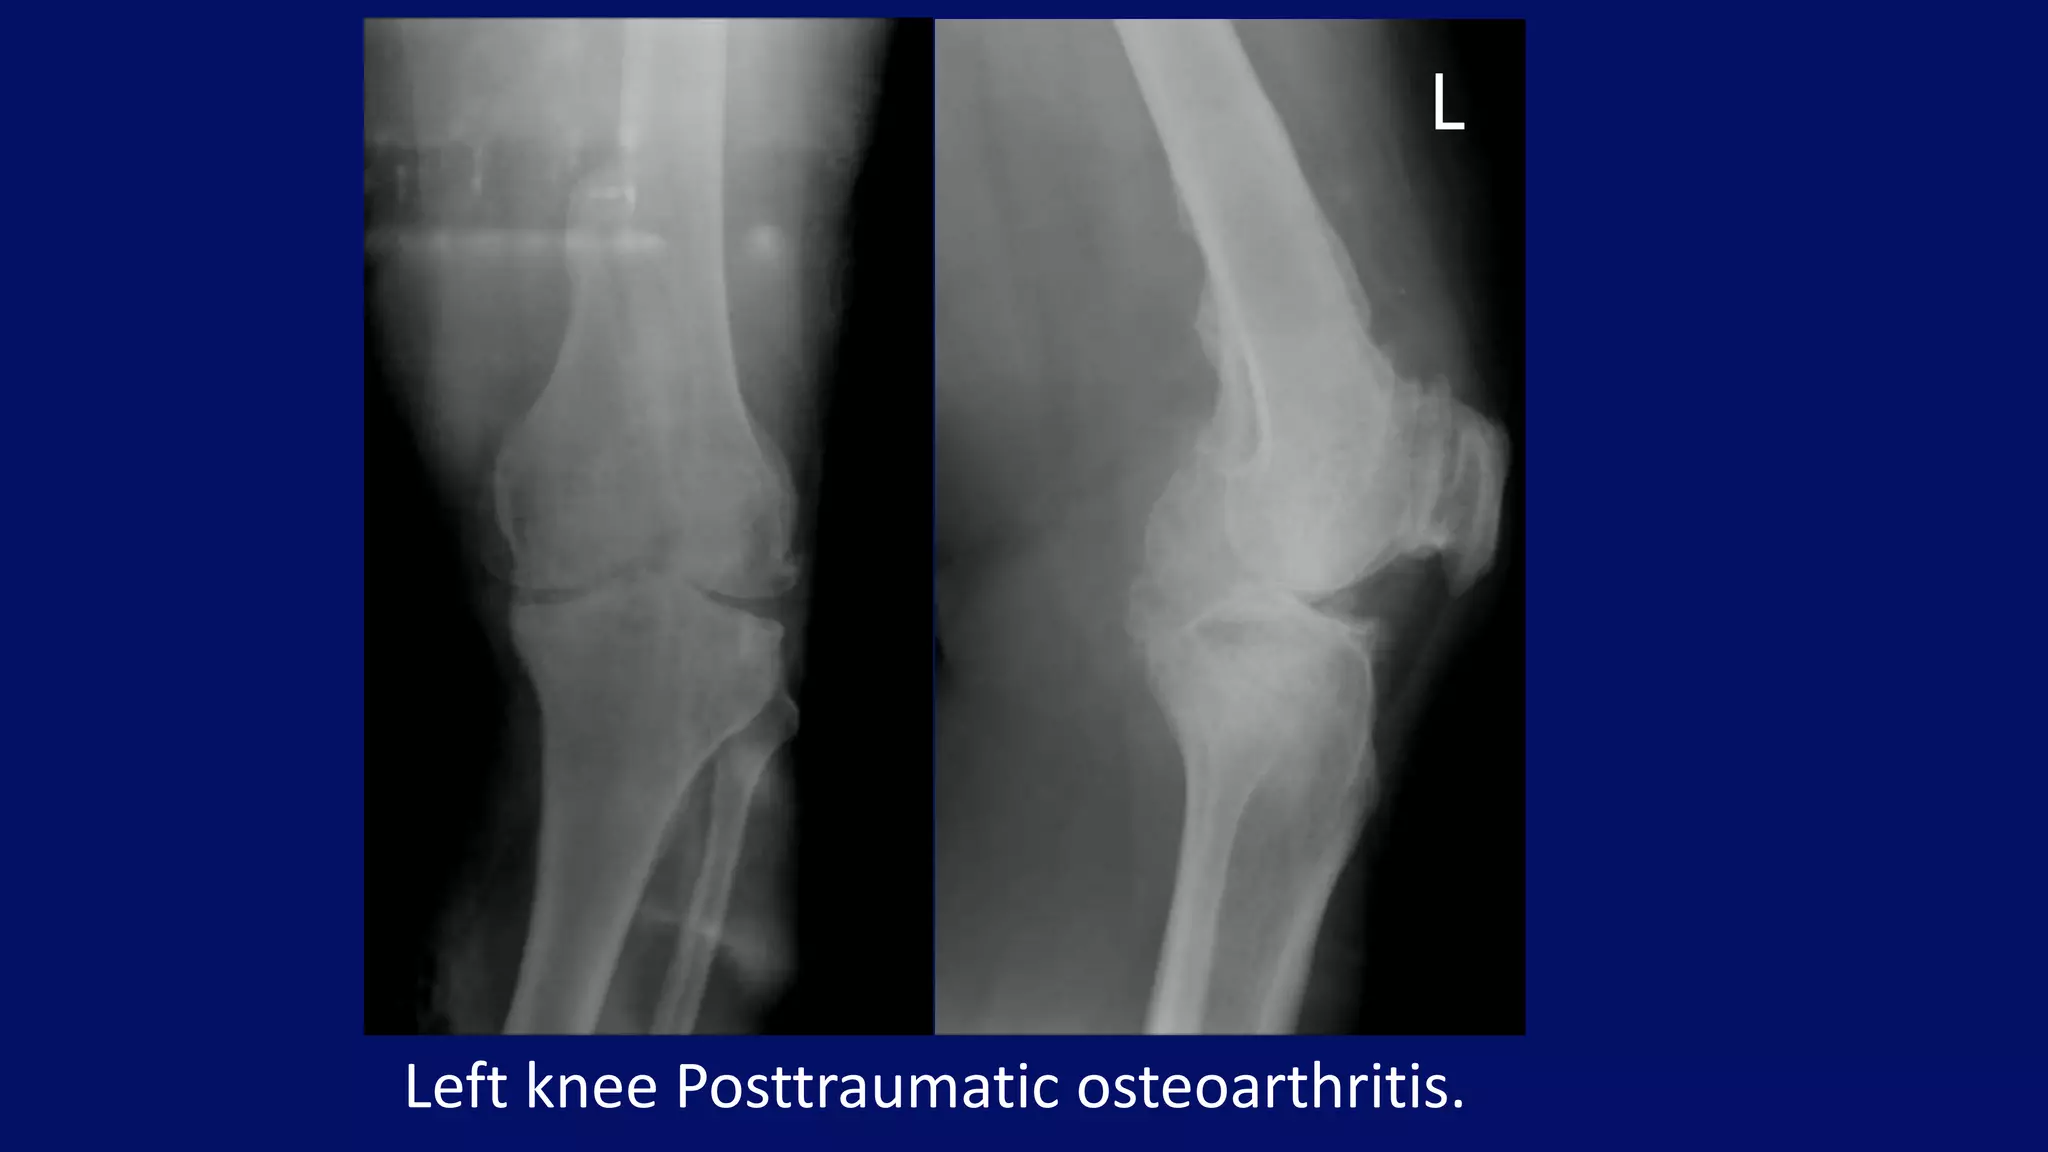

• most common cause of secondary/atypical

osteoarthritis

• changes similar to those in primary osteoarthritis

• history of previous trauma

• younger age group

Posttraumatic Osteoarthritis

Left knee Posttraumatic osteoarthritis.

L